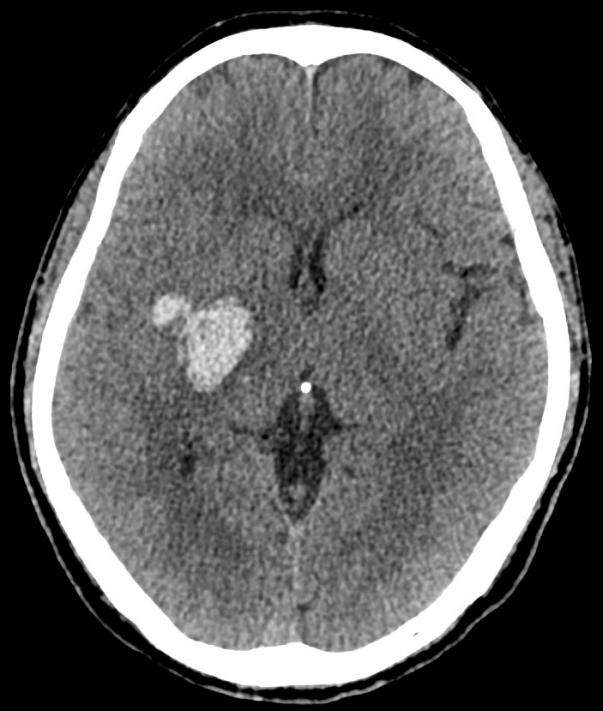

2. CT检查:CT检查具有更高的密度分辨率和空间分辨率,能够发现更细微的病变。在肺部疾病的诊断中,CT尤其是高分辨率CT(HRCT),可以清晰地显示肺部的微小病灶,对于早期肺癌的筛查具有重要意义。通过CT检查,医生能够观察到肺部小结节的大小、形态、边缘、内部结构等特征,从而判断其良恶性。在神经系统疾病方面,CT可用于检查脑出血、脑梗死、脑肿瘤等。在腹部疾病诊断中,CT对肝脏、胆囊、胰腺、脾脏等器官的病变也有很好的显示效果,如肝囊肿、肝癌、胆结石、胰腺炎等。

左肺上叶肺结节和右侧基底节脑出血